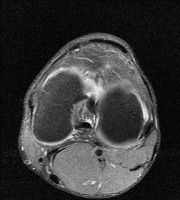

무릎 mri 간단히 봐주실 수 있으시나요 ㅠㅠ

안녕하세요 8년전 십자인대 수술하고 최근 무리한 운동에 무릎 불편감이 생겨서

mri 찍었습니다.

진단결과는 첫 찍은 병원에서 활액막염 이라는 진단을 받았습니다. 혹시 봐주실 수 있으실까요?

올라온 MRI가 단편적이라서 정확한 진단에 어려움이 있지만 십자인대에는 큰 이상이 있지는 않은것 같으며, 무릎관절내 물이 있는 것으로 보아 활액막염의 진단이 맞을 것 같습니다.

하지만 단편적인 영상이기 때문에 촬영병원에서 정확한 판독지 등을 받으시는 것이 좋겠습니다.